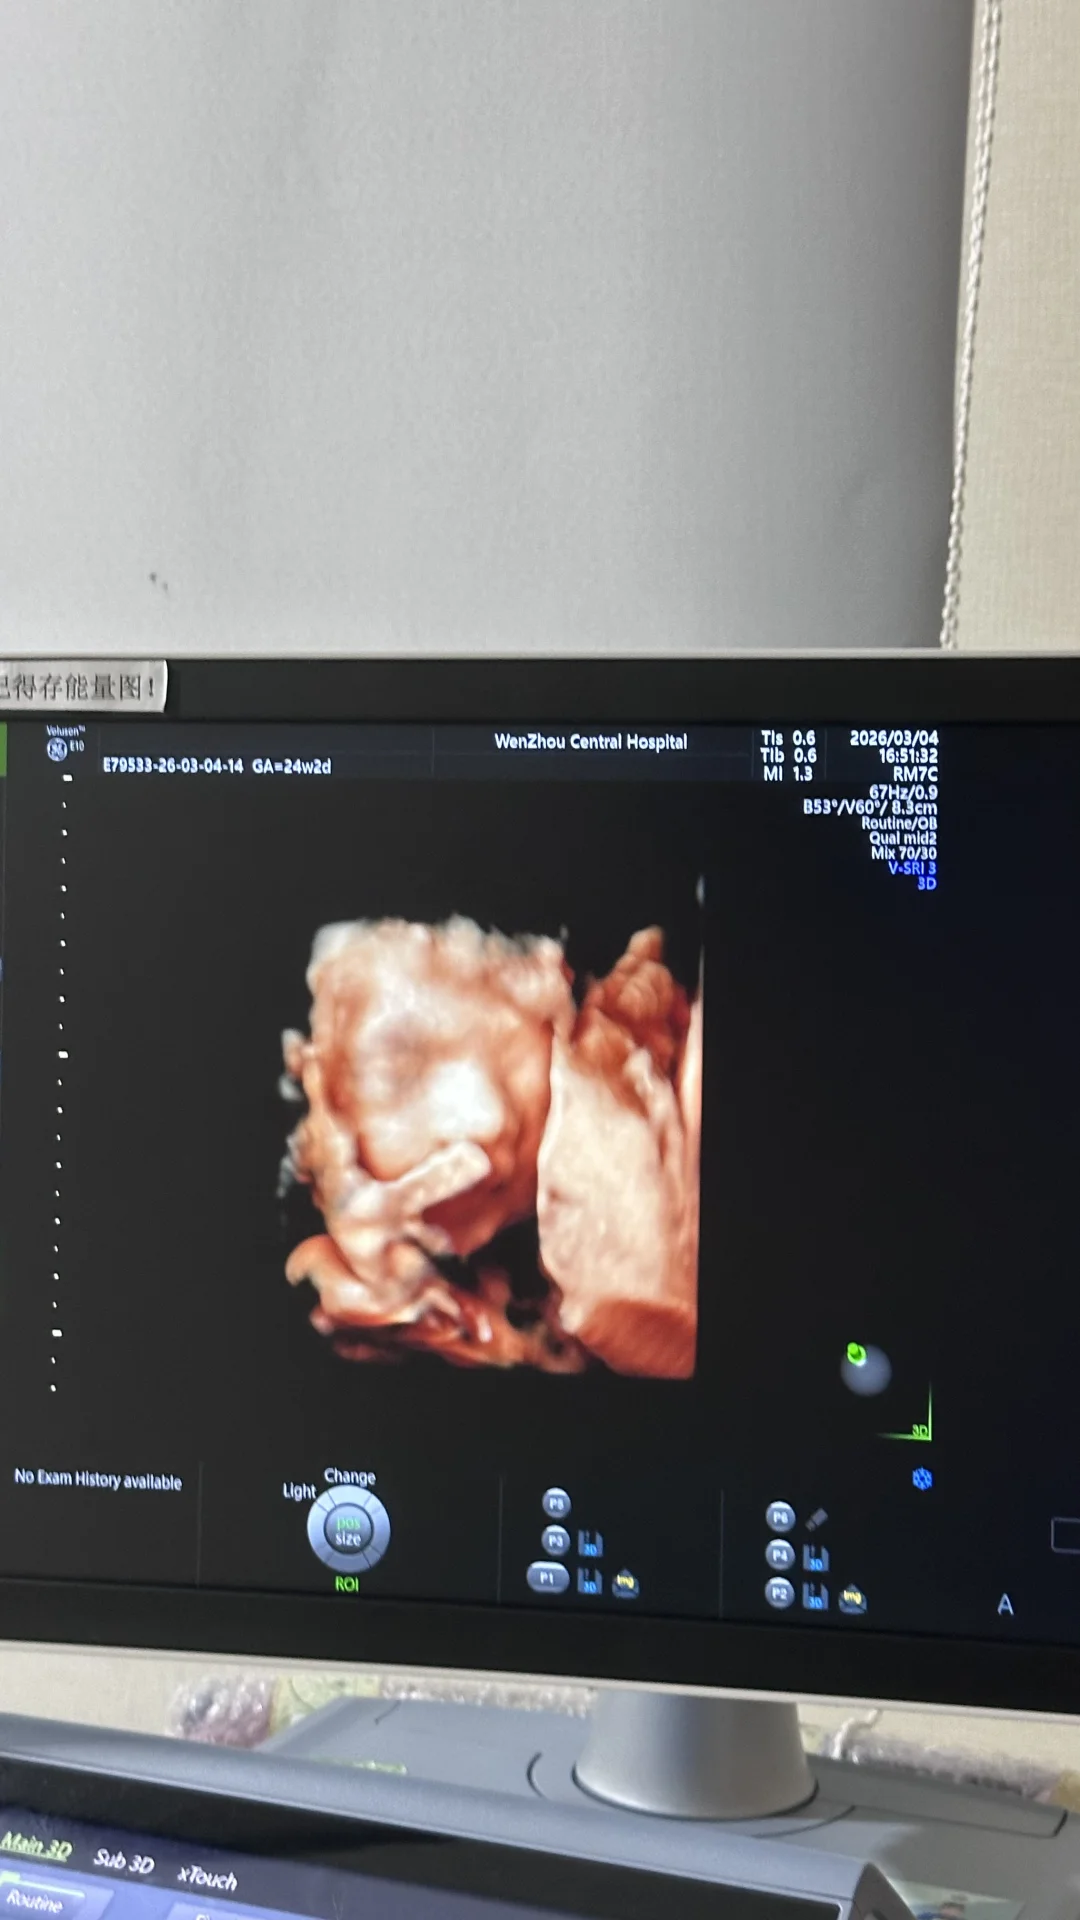

终于和宝宝见面了 💜孕中期四维照

愿姐妹们也一路绿灯~ 好孕相伴 长年的瑜伽普拉提陪伴让整个孕期都充满了活力💖